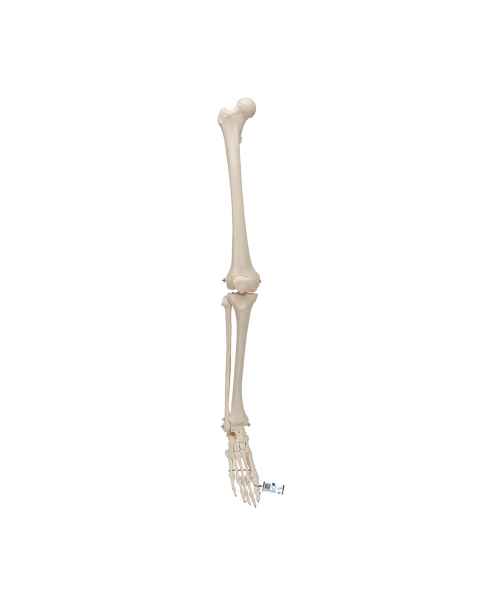

Extremity Models

While the majority of vital human organs are located inside of the head and torso, human appendages are just as important in terms of day-to-day functionality. In order to depict the parts and workings of these limbs, doctors and teachers rely upon extremity anatomical models.

With the assistance of extremity anatomy models, patients and students have a tangible tool to better understand their appendages, as well as potential injuries that are afflicting them or require treatment. Our extensive selection of extremity models includes arm anatomical models, foot models, hand anatomy models, and leg models.